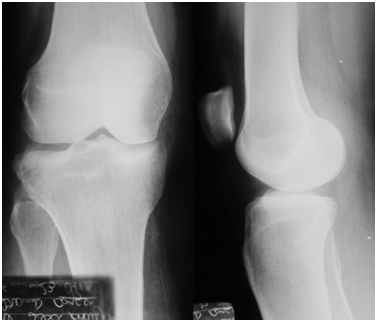

Knee radiographs revealed the Segond fracture (Figure 1A & 1B). The patient underwent an MRI and a computed tomography (CT). Both CT and MRI showed the Segond fracture. The MRI showed integrity of the ACL, posterior cruciate ligament (PCL), medial collateral ligament (MCL), posterolateral corner (PLC) structures and menisci (Figure 2A-2E).

Figure 1 A: Anteroposterior radiography demonstrating the Segond fracture. B: Lateral radiograph